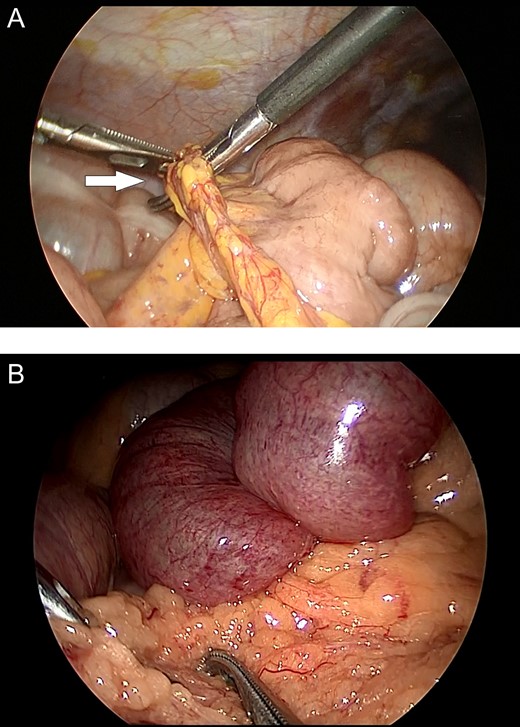

The first patient was a 58-year-old female who presented to our hospital with abdominal pain and vomiting; she had no history of abdominal surgery. Upon performing an examination, her abdomen was soft, with no guarding or rebound tenderness; however, central abdomen palpation revealed tenderness. A laboratory investigation revealed no abnormalities; however, enhanced abdominal computed tomography (CT) revealed intestinal obstruction of the right lower quadrant with the beak sign, indicating the transition zone of SBO (Fig. 1A). Therefore, the patient was diagnosed with strangulation ileus due to the internal hernia. Emergency laparoscopic surgery revealed an incarcerated loop of the small bowel through a greater omental defect (Fig. 2A). The incarcerated small bowel was released; because the ileal segment was viable, bowel resection was deemed unnecessary. The patient was uneventfully discharged on postoperative Day 8.

Intraoperative images. (A) Incarceration of a loop of the small bowel through a defect in the greater omentum (arrow). (B) Small bowel loops appear to be congested and herniate through the greater omentum.

The second patient was a 36-year-old male who presented to our hospital with abdominal pain and had no history of abdominal surgery. His physical examination revealed upper abdominal tenderness. Laboratory investigations revealed no abnormalities except for an abnormal white cell count (11 000 mm3). Enhanced abdominal CT revealed dilated, fluid-filled loops of the small bowel, with caliber change in the upper abdomen (Fig. 1B and C). He was suspected of having transomental hernia, and emergency laparoscopy was performed. During surgery, an ileal segment measuring ~15 cm in length was observed to be herniating through a greater omental defect (Fig. 2B). The small bowel was released by dividing the omentum; there was no evidence of ischemic changes in the incarcerated loop of the small bowel. The postoperative course was uneventful; the patient was discharged on postoperative Day 4.